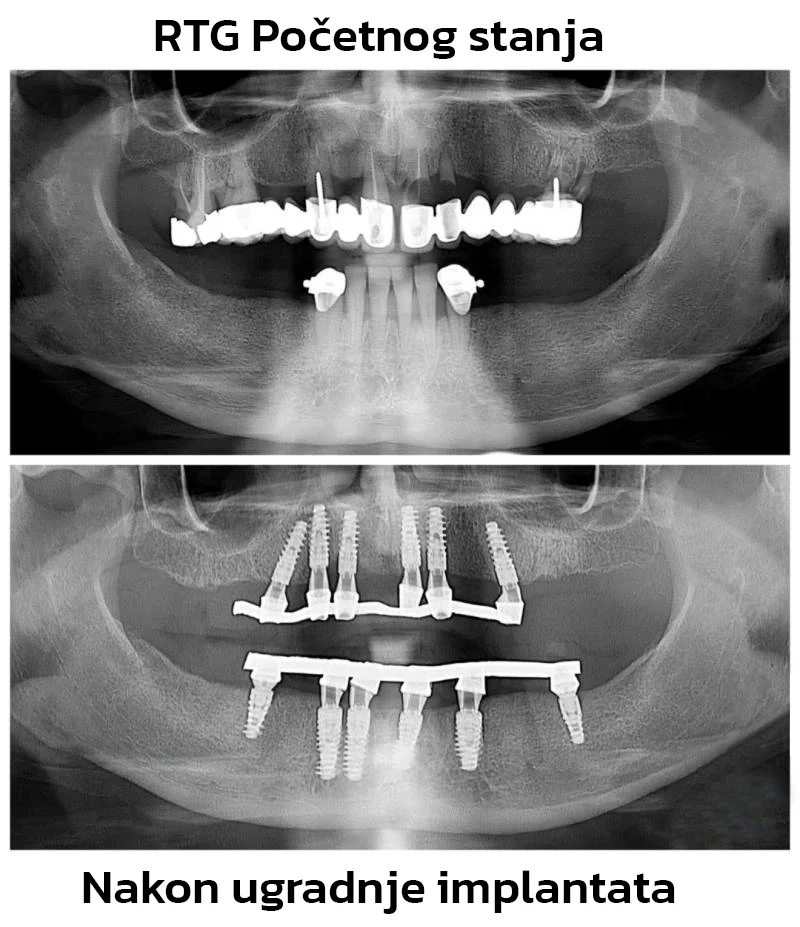

Implantat je mali titanijumski “korijen” koji se postavlja u kost. Tijelo zatim radi svoj dio: oko implantata se stvara stabilna veza s kosti (proces koji se zove oseointegracija). To se ne “osjeti” kao rana, ali je ključan dio cijelog puta.